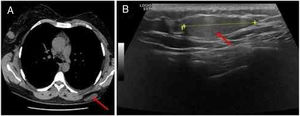

Tomografia computadorizada torácica de alta resolução, realizada um ano antes durante um episódio de agudização de asma, revelara um nódulo subcutâneo hipodenso de grandes dimensões na localização topográfica referida (fig. 1A). Biópsia por agulha grossa e ecoguiada daquela massa subcutânea bem definida e ligeiramente hiperecogênica identificou uma neoplasia de células globosas, algumas com citoplasma multivacuolado e outras com citoplasma granular, eosinofílico, sem atipia nuclear (fig. 1B).

Características imagiológicas do tumor: A, Tomografia computadorizada torácica de alta resolução revelando nódulo subcutâneo hipodenso de grandes dimensões na região dorsal esquerda (seta vermelha); B, Ecografia revelando massa subcutânea bem definida, ligeiramente hiperecogênica, na região dorsal esquerda (seta vermelha).